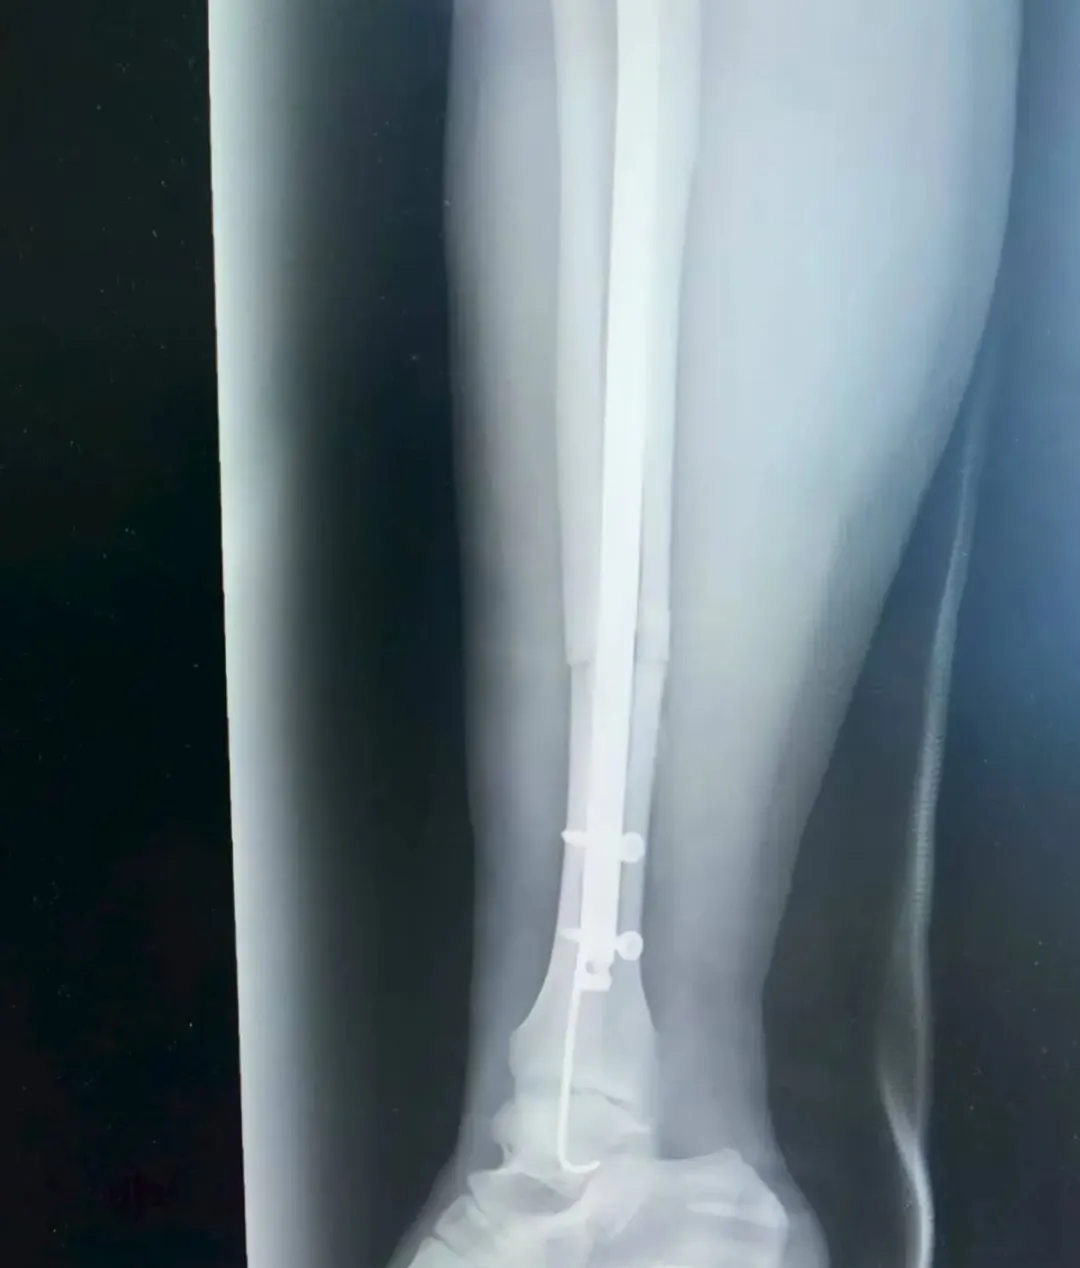

考虑到张女士是外地游客,不仅希望骨折能精准复位,还盼着创伤小、恢复快,不耽误后续返程与康复。董伟副主任医师结合影像学资料,综合考虑张女士的身体状况与个人需求,最终确定采用“胫腓骨骨折闭合复位+胫骨髓内钉内固定术+腓骨髓内针内固定术”,全程无需做大切口,通过微创方式实现骨折端精准对位,既能最大程度保护肿胀的软组织,又能显著提升术后恢复速度。

精细手术操作

手术由董伟、孙毅珲共同完成,术中借助C臂机实时透视引导,小心翼翼地通过闭合复位技术调整骨折端位置,确保达到解剖复位标准;随后精准植入胫骨髓内钉与腓骨髓内针,完成固定。整个手术过程出血少,术后仅留下几个微小创口,最大程度减少了张女士的痛苦。